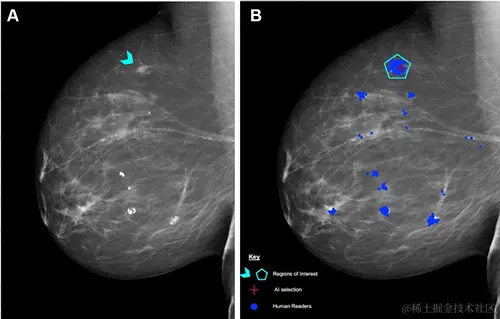

图 6:不同阈值对 AI 判断结果的影响

A:蓝色箭头为不对称区域,后鉴定为组织学 2 级导管癌;

B:AI 阈值为 2.91 时的检测结果,红色十字最终鉴定为真阳性;

C:AI 阈值为 3.06 时的检测结果,没有发现明显异常特征。